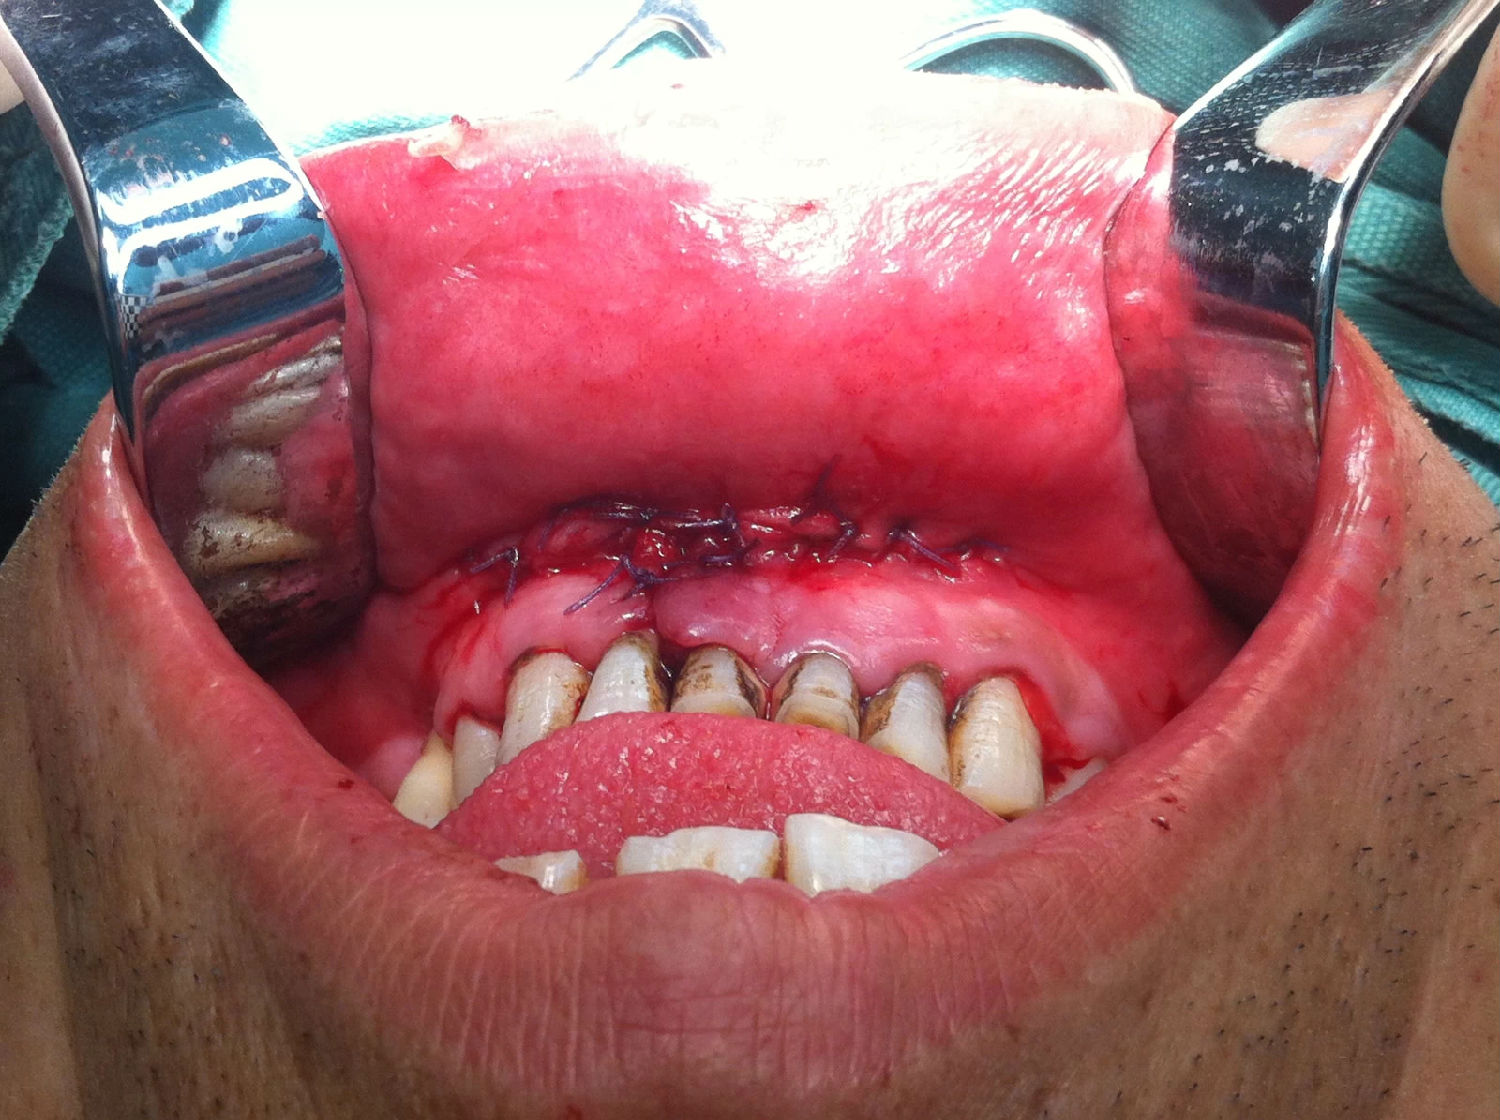

入院后全麻下手術(shù)治療,左側(cè)下頜骨囊腫較大,術(shù)前考慮病理性骨折可能,準(zhǔn)備鈦釘鈦板固定,術(shù)中摘除囊腫后,發(fā)現(xiàn)下頜骨下緣骨量尚可,未給予固定。術(shù)后病理診斷為下頜骨角化囊腫,考慮到患者可能為基底細(xì)胞癌綜合征,術(shù)中切除頸部皮膚痣兩處,術(shù)后病理診斷為:皮膚痣,排除基底細(xì)胞癌綜合征?;颊哂凶髠?cè)第六肋骨分叉肋,綜合以上特征,最終診斷為多發(fā)性頜骨囊腫綜合征。

以上為術(shù)中所拔出患牙及剝離的頜骨囊腫。

另附一例上腭多行性腺瘤一例。